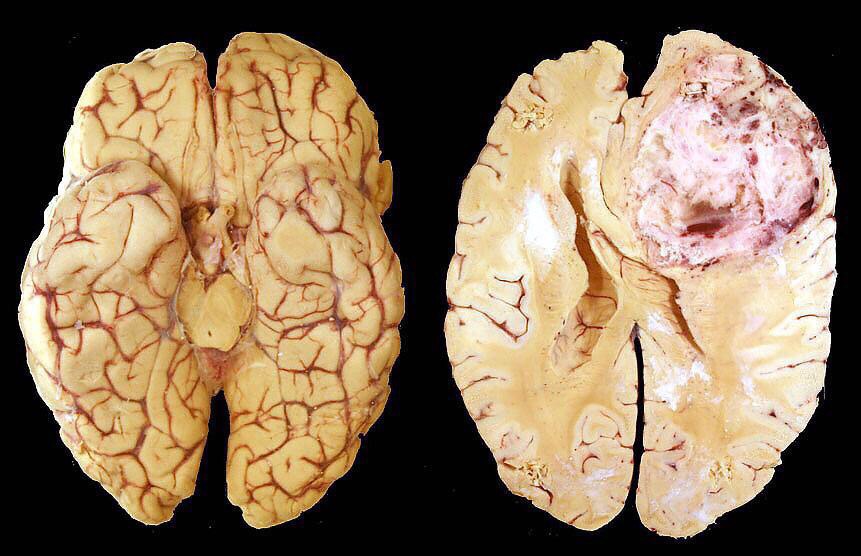

血管母细胞瘤,但以囊性者多见。约占80%。囊性血管网状细胞瘤多见于小脑半球。而实质性者多见于脑干,脊髓及小脑蚓部等中线结构。

完整切除肿瘤。

手术用时3小时55分钟.完整切除肿瘤。

术后,肿瘤全切,效果满意。